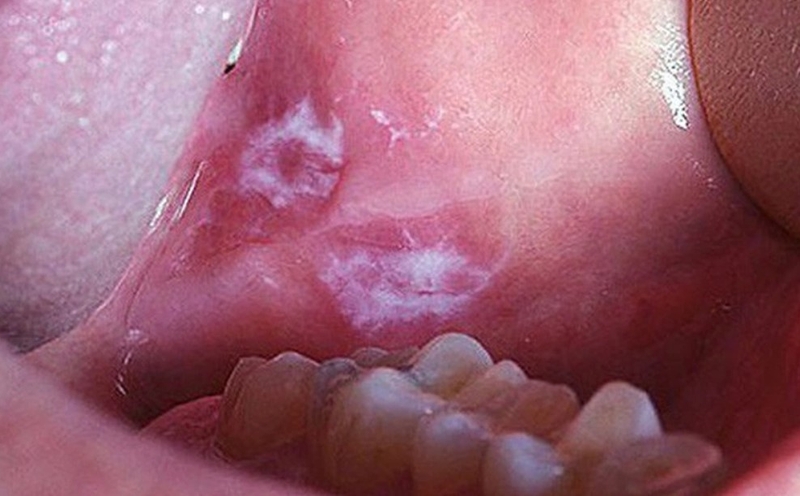

Lichen phẳng là bệnh lý viêm mãn tính ở miệng, xảy ra do hệ thống miễn dịch của cơ thể tấn công các tế bào trong màng nhầy. Lưỡi có đốm trắng là dấu hiệu thường gặp của bệnh lý này, bao gồm các mảng trắng giống như chất liệu ren.

Bệnh lý này xuất hiện chủ yếu ở đối tượng bị suy giảm miễn dịch, người già và phụ nữ trung niên. Một số nguyên nhân bệnh có thể do:

Nếu nghi ngờ mình mắc phải bệnh Lichen phẳng với biểu hiện lưỡi có đốm trắng, bạn cần nhanh chóng đến cơ sở y tế để được thăm khám và thực hiện sinh thiết để kết luận chính xác tình trạng bệnh.